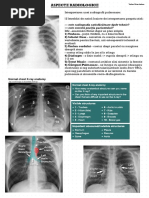

Radiografia toracica in dinamica

Radiografia toracica- 2013 Radiografia toracica- 2015

Radiografia toracica- 2018 Radiografia toracica- 2018

Bronsiectazii bilaterale. Modificari fibrotice in lobii superiori.

Aspergilom intracavitar lob superior pe dreapta. Sechele posttbc.